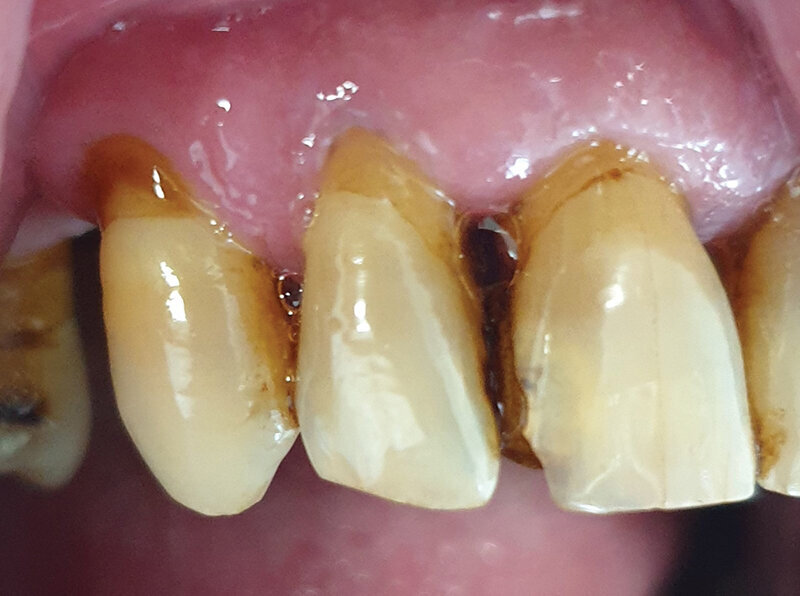

Pacijent A pušač pri prijemu. Jasno se uočavaju naslage u vidu estetski neprihvatljivih pušačkih pigmentacija na svim površinama zuba. Nizak nivo oralne higijene ogleda se u nalazu zubnog kamenca i visokom Plak indexu. Jasno su uočljive pušačke melanoze vidljivog dela desni kao i suvoća i beličaste promene obraznog dela sluzokože. Obložen jezik takođe je karakterističan nalaz višegodišnjeg pušača (Sl. 1.0).

Sl. 1.0: Pacijent A, pušač pri prijemu